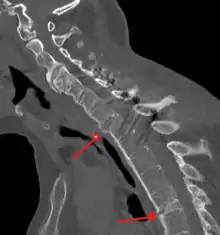

Imaging

X-rays

The earliest changes demonstrable by plain X-ray shows erosions and sclerosis in sacroiliac joints. Progression of the erosions leads to widening of the joint space and bony sclerosis. X-ray spine can reveal squaring of vertebrae with bony spur formation called syndesmophyte. This causes the bamboo spine appearance. A drawback of X-ray diagnosis is the signs and symptoms of AS have usually been established as long as 7–10 years prior to X-ray-evident changes occurring on a plain film X-ray, which means a delay of as long as 10 years before adequate therapies can be introduced.[24]

Options for earlier diagnosis are tomography and MRI of the sacroiliac joints, but the reliability of these tests is still unclear.

Lateral X-ray of the neck in ankylosing spondylitis

CT scan showing bamboo spine in ankylosing spondylitis